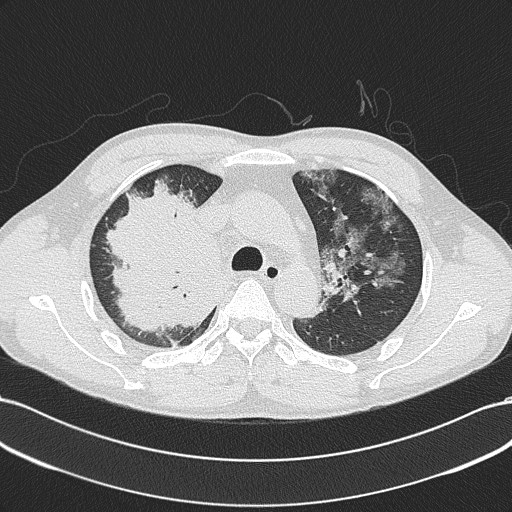

2013-05-06 chest CT(2)